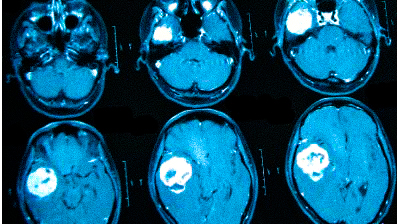

Онкологи считают, что при нарастающих головных болях с прочими необъяснимыми симптомами (обмороками, ухудшением памяти, выпадением полей зрения, давлением на глазные яблоки и др.) в первую очередь следует исключить опухолевую патологию

Частые головные боли вызывают разные причины. Иногда так проявляется серьезное заболевание. В 90% случаев после определения генеза возможно адекватное лечение, которое улучшит качество жизни. Состояния, для которых типична цефалгия::

опухоли;

Если причина не установлена, обосновано прохождение МРТ головы при головных болях. Не стоит подозревать у себя смертельную патологию. Например, если болит затылок, возможной причиной является переутомление, а нормализация режима труда и отдыха поможет справиться с проблемой. При повышенном давлении часто присутствует головокружение, покраснение кожных покровов, шум в ушах. Боль в лобной части головы вторична и проходит после приема гипотензивного лекарства. Но гипертония может быть связана с патологией сосудов или опухолевой компрессией, поэтому прохождение МРТ при сильных головных болях — важный аспект в дифференциальной диагностике.